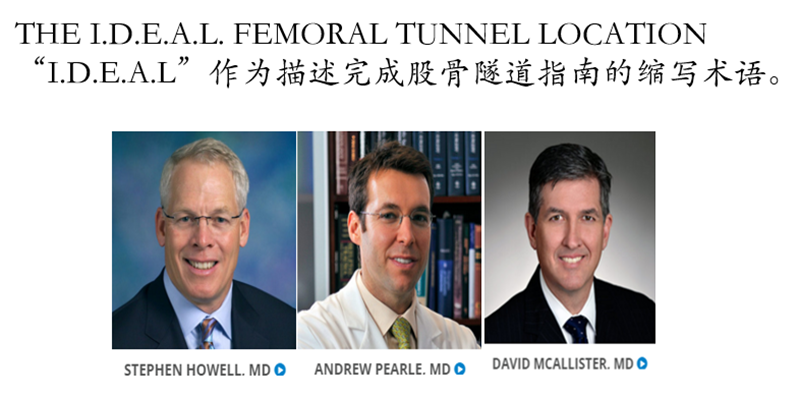

交叉韧带重建理念与技术的变迁:等长-解剖-类等长-功能束重建-“I.D.E.A.L”。三位外科医生在ACL重建领域加起来拥有70年的临床和研究经验。作为一个团队,他们对大量ACL重建解剖学,组织学,生物力学和临床数据进行了全面研究,并推荐使用首字母缩略词“I.D.E.A.L”作为描述完成股骨隧道指南的缩写术语。

I.D.E.A.L. femoral tunnel location (黑色圆圈位置为理想股骨骨道位置)。